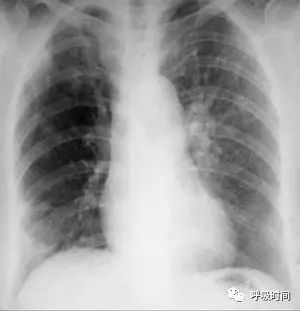

图 1 为胸部正侧位片

双肺(血管)纹理清晰(至胸膜下 3 cm / 限于肺野中内带);肺门结构不大、清晰。心影大小形态无异常,纵隔无偏移。双侧肋膈角锐利,胸廓对称